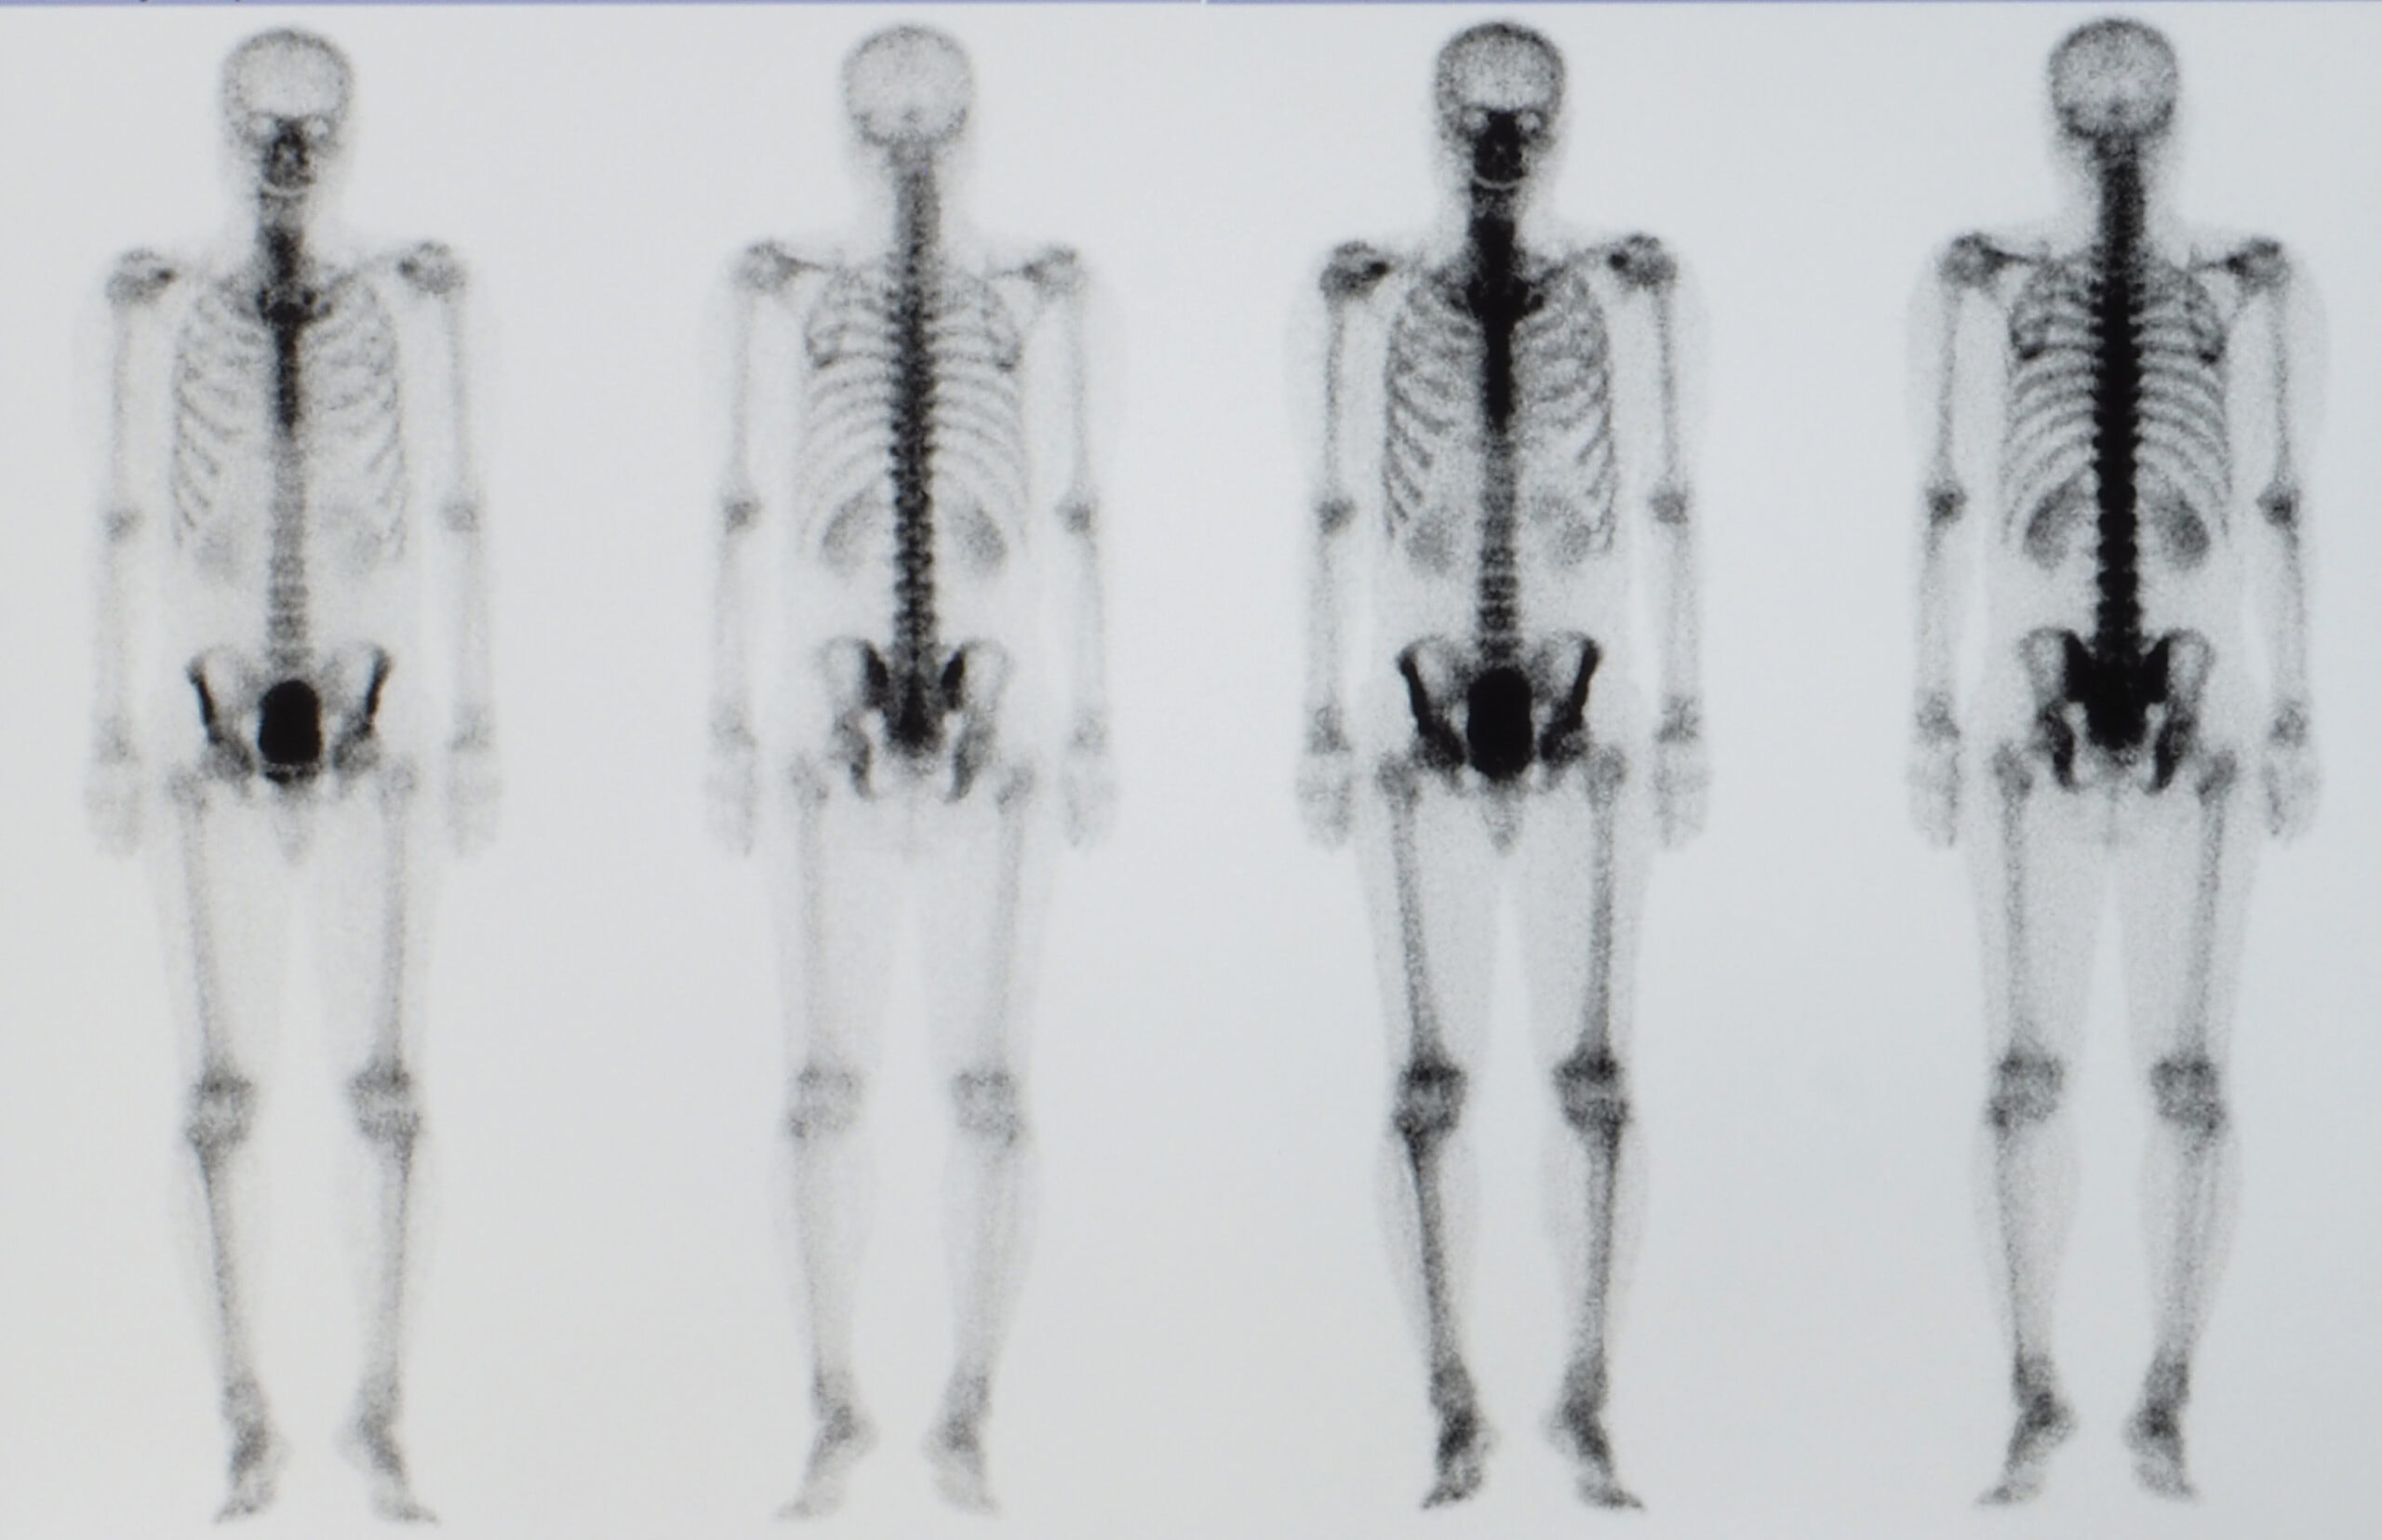

A cintilografia óssea de corpo total é um exame de Medicina Nuclear que permite avaliar o metabolismo e a integridade do esqueleto humano. Para isso, utiliza-se uma substância levemente radioativa (radiofármaco), que é injetada na veia do paciente.

Esta substância circula pela corrente sanguínea e se fixa em regiões doentes dos ossos. As imagens revelam alterações ósseas que podem indicar fraturas, infecções, inflamações ou a presença de tumores.